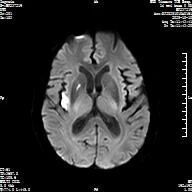

卒中中心立即启用脑卒中绿色通道,快速完成生命体征评估、静脉通路建立和血液标本采集等工作,在进行一站式头颅CT+头颅磁共振相关检查后,医生诊断该患者为“急性脑梗死”,此时距离发病已超过8小时,远超传统4.5小时溶栓“时间窗”,经神经内科、影像科等多学科专家紧急会诊、联合评估,确认患者符合“超时间窗”静脉溶栓指征,在征得患者家属同意后,为患者实施了静脉溶栓治疗。

静脉溶栓治疗24小时后患者肢体偏瘫、吐词不清明显好转,出院时患者已经可以自已行走。